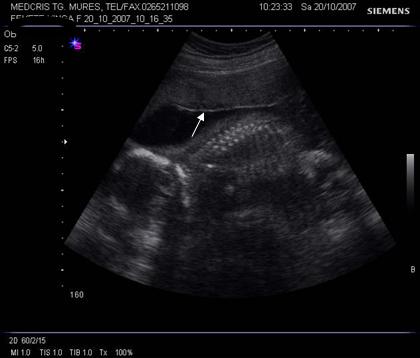

Fig. nr.205. Placenta fundica si posterioara ( normal inserata, cu sageata ) la o sarcina de 16 sapt.